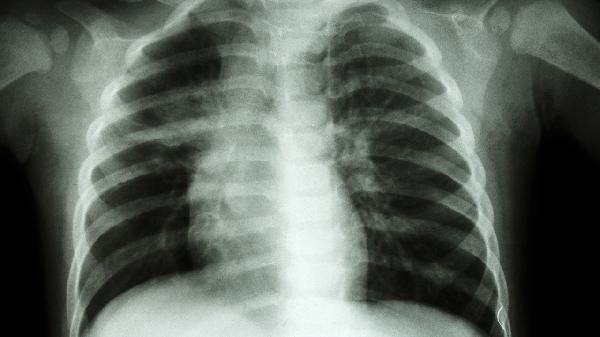

15岁肋骨一边凸起可能与脊柱侧弯、佝偻病、外伤、肋骨发育异常或胸廓畸形等因素有关。建议及时就医,通过影像学检查明确诊断。

青少年特发性脊柱侧弯是常见原因,可能与遗传、激素水平或神经肌肉控制异常有关。表现为背部不对称、肩胛骨突出,伴随肋骨旋转性隆起。轻度可通过矫形支具矫正,中重度需手术干预如后路脊柱融合术。可遵医嘱使用布洛芬缓释胶囊缓解疼痛。

维生素D缺乏导致骨软化,可能形成肋骨串珠样凸起。多与日照不足、饮食摄入不足相关。需补充维生素D滴剂和碳酸钙D3片,配合每日户外活动。家长需定期监测血钙磷水平。

肋骨骨折愈合不良可能形成骨痂隆起。需通过CT三维重建评估愈合情况,陈旧性骨折畸形严重时需手术修整。急性期可遵医嘱使用对乙酰氨基酚片镇痛。

先天性肋骨融合或分叉畸形可能导致局部隆起,通常无疼痛症状。CT可显示肋骨形态异常,影响呼吸功能时需手术切除畸形肋骨段。

漏斗胸或鸡胸可能伴随单侧肋骨突出,与遗传性结缔组织发育异常有关。严重者需行Nuss手术或胸骨翻转术矫正,轻度可使用真空吸盘保守治疗。